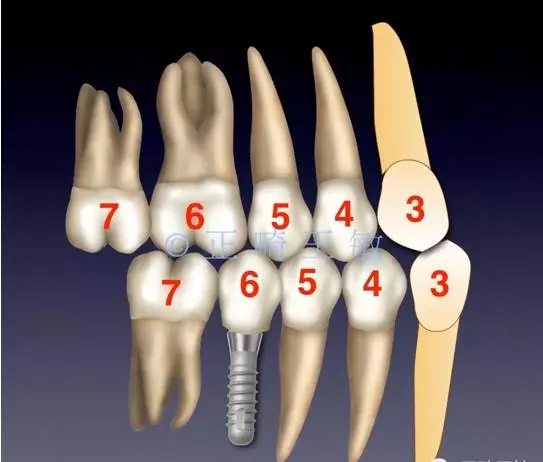

這時,順理成章的種一個小一點的46,同樣是尖窩相對,同樣的穩(wěn)定。